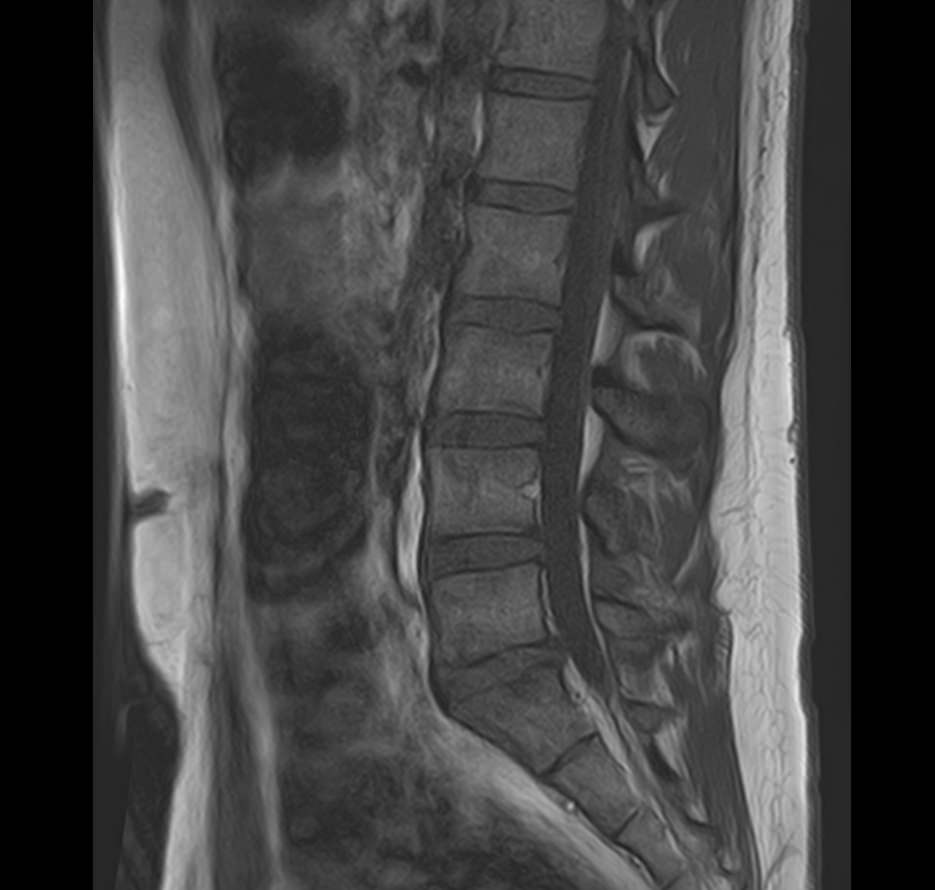

Боли в спине являются наиболее распространенными симптомами различных заболеваний позвоночника. При этом боли могут беспокоить сразу в нескольких сегментах позвоночного столба, включая его рудиментарную часть – копчик. Причинами появления таких симптомов могут быть воспалительные процессы, дегенеративно-дистрофические заболевания позвоночника, травматические повреждения и опухолевые поражения данных анатомических областей.

При подозрении на распространенный процесс с поражением различных уровней позвоночника в клинике «Доступная медицина» возможно проведение комплексной МРТ всего позвоночника – 3 отдела + копчик.

Магнитно-резонансная томография является наиболее чувствительным и эффективным методом диагностики различных заболеваний позвоночника. Метод позволяет оценить состояние костных структур позвонков, позвоночного канала с расположенным в нем спинным мозгом и окружающих мягких тканей, кроме того является основным способом диагностики демиелинизирующих заболеваний спинного мозга.

Данное комплексное обследование позволяет выявить следующие патологические состояния:

• Дегенеративные-дистрофические заболевания в шейном, грудном, пояснично-крестцовом отделах позвоночника и копчике (спондилез, спондилоартроз, остеохондроз).

• Грыжи межпозвонковых дисков (протрузии, экструзии).

• Стеноз (сужение) позвоночного канала.

• Травматические повреждения позвоночника, спинного мозга, связочного аппарата, близлежащих мягких тканей.

• Доброкачественные и злокачественные опухоли спинного мозга, костей, нервных корешков или мягких тканей, окружающих позвоночник.

• Инфекционные и воспалительные заболевания позвоночника и спинного мозга (спондилиты, гнойные артриты, абсцессы околопозвоночных тканей, туберкулез).

• Демиелинизирующие заболевания спинного мозга.

• Патологические изгибы позвоночника, сколиоз, усиленный или выпрямленный лордоз как нарушение статической функции позвоночника.

• Аномалии развития позвоночника.